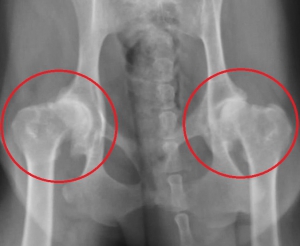

下は股関節の進行した変形性関節症のレントゲン写真です。赤丸の中が股関節ですが、大腿骨頭は変形して、関節内には骨棘の形成がみられます。同じ部位の正常写真が右です。

このワンちゃんは日常的に下肢の痛みを訴えており、運動状態によって、また寒い時期に悪化がみられます。後ろ足には常に痛みがあり、充分に動かすことができません。